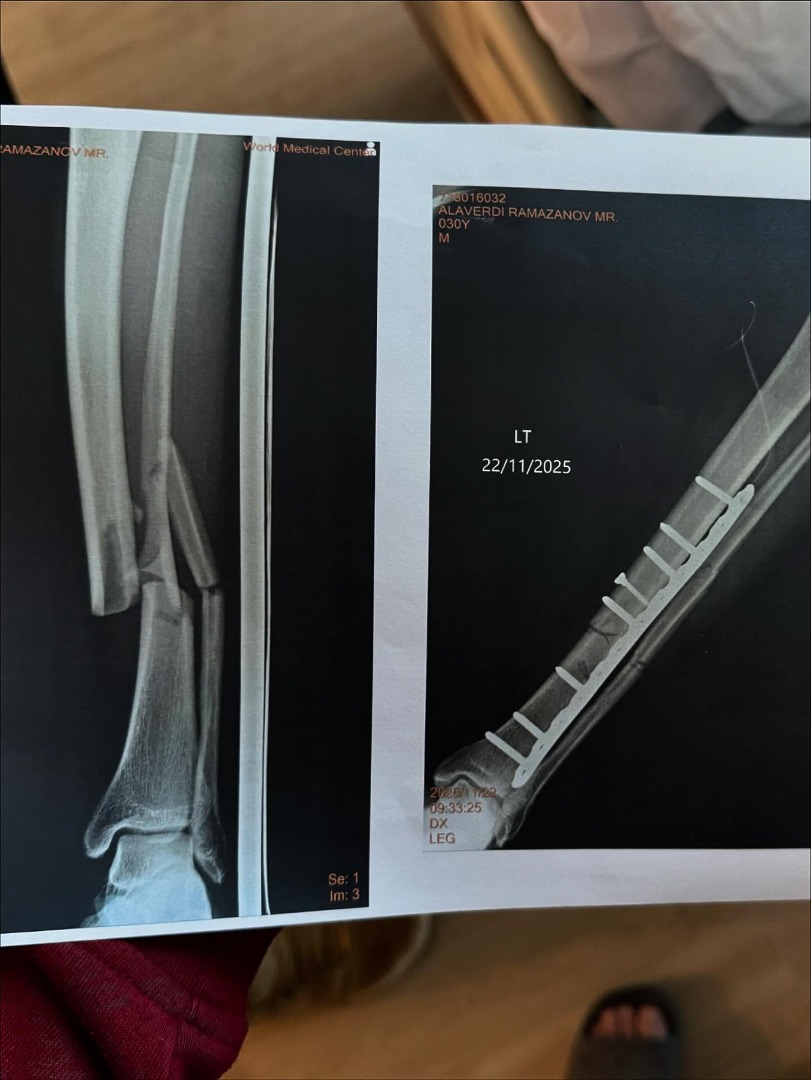

ล่าสุด อลาเวอร์ดี รามาซานอฟ ได้โพสต์ภาพหลังการเข้ารับการผ่าตัด และฟิล์มเอกซเรย์ พร้อมข้อความ "การผ่าตัดประสบความสำเร็จอย่างราบรื่น ขอขอบคุณ ONE เป็นพิเศษสำหรับการดูแลที่ดี และขอขอบคุณทุกคนที่อยู่กับฉันด้วย"